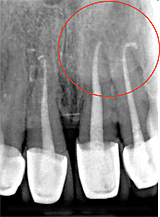

Zweitbehandlung (Revision)

Sollten nach einer bereits durchgeführten Wurzelbehandlung noch Keime im Zahn zurück bleiben, z. B. durch nicht aufbereitete Wurzelkanäle oder nicht vollständig gereinigte Wurzelkanäle, dann können diese später eine chronische, aber auch eine akute Entzündung an der Wurzelspitze auslösen.

In diesem Fall sollte eine erneute Behandlung (Revision) durchgeführt werden. Der Ablauf entspricht dem oben beschriebenen, zusätzlich wird die bestehende Wurzelfüllung entfernt und die Aufbereitung und Reinigung der Wurzelkanäle wiederholt.

Oberkieferschneidezähne mit z. T. unvollständiger Wurzelfüllung und chronischer Entzündung an den Wurzelspitzen und Ausheilung nach 11 Monaten